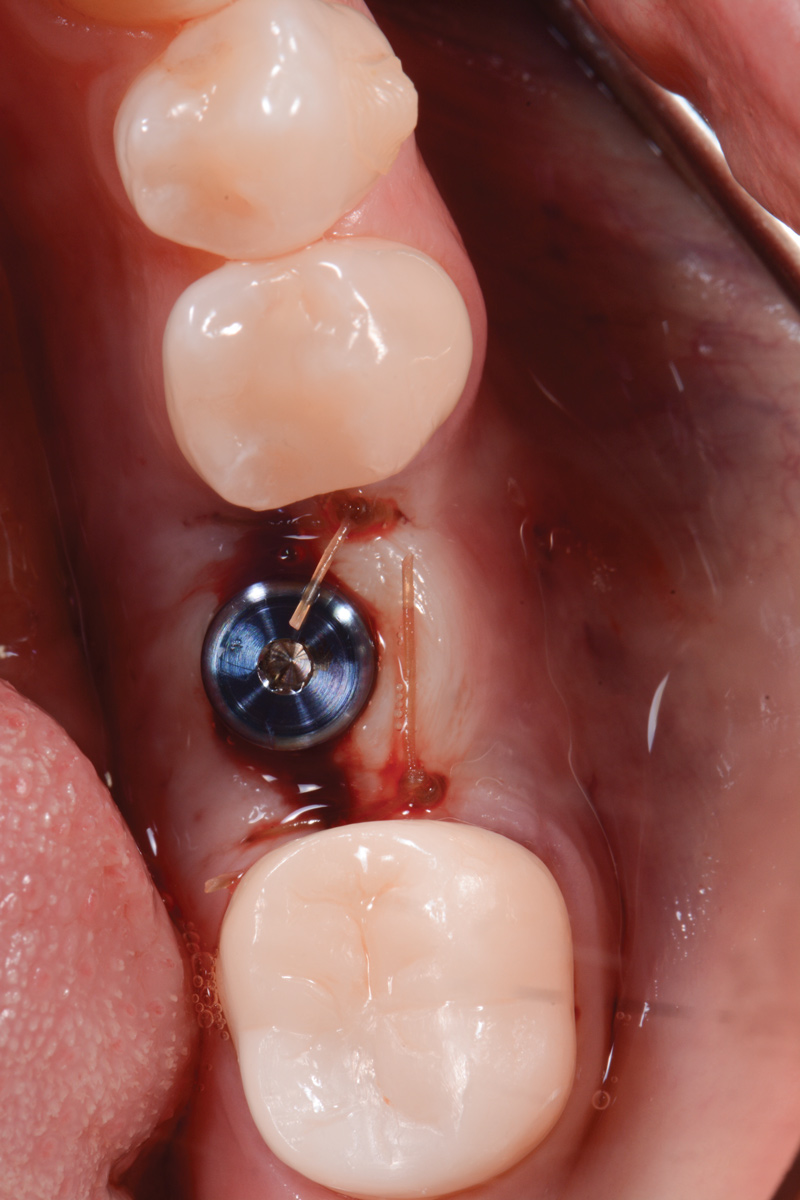

The following day, the patient presented for an emergency, reporting she began to bleed after she left the office and had continuous bleeding that day and night. Vital signs were normal (blood pressure was 115/65 mmHg, and pulse was 53 beats per minute). The first attempt to control the bleeding included having the patient bite on wet collagen wound dressing and alternate using wet- and dry-gauze compression for 30 minutes. After the removal of the collagen wound dressings, the bleeding restarted spontaneously. The sutures were then removed, and a collagen wound dressing was placed under the flap. Two single interrupted sutures were used, and a third suspended suture was placed around the healing abutment to obtain compression in the area. The patient was observed for 1 hour. During this time, wet-gauze compression was used on the area until the bleeding stopped. The patient was then dismissed and told to reapply gauze with pressure if bleeding recurred (Figure 1 through Figure 5).

Fig 3. Wound dressing in place.

Figure 3